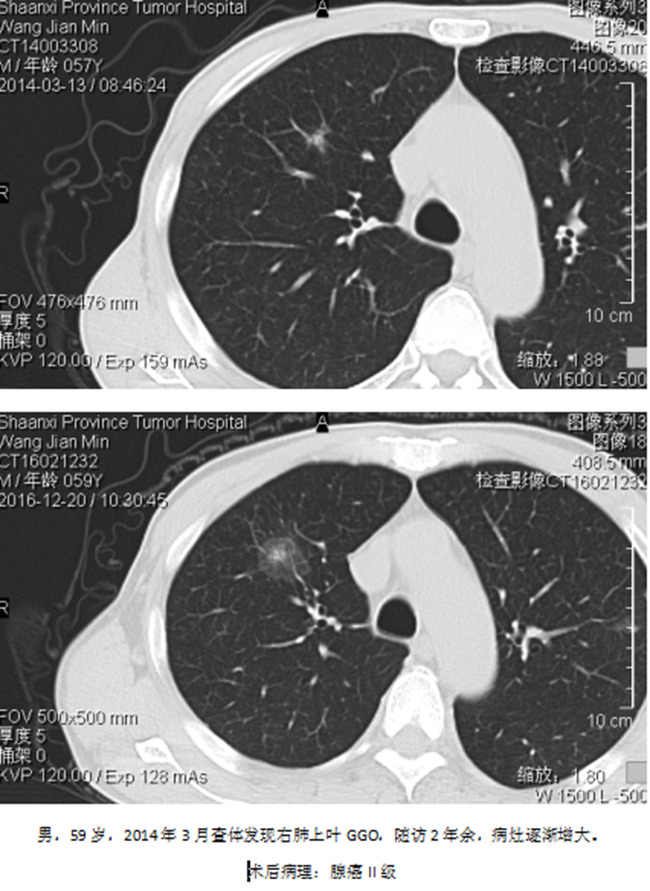

5、CT定位穿刺活检

这是一个具有争议性话题,有人不建议,认为并发症多,阳性率率低。我们认为,要看病灶的大小,部位,具体的病灶具体对待,不能一概而论。CT定位穿刺活检可以确定病灶的良恶性,对指导治疗是很有益的。

穿刺案例: